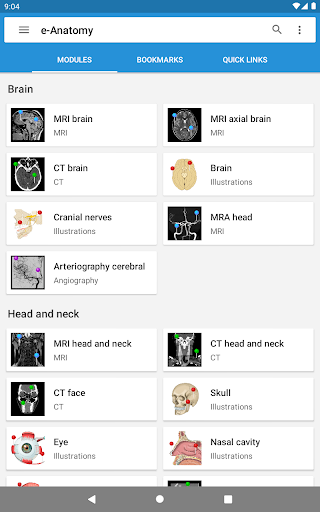

IMAIOS e-Anatomy adalah atlas anatomi manusia untuk dokter, ahli radiologi, mahasiswa kedokteran, dan teknisi radiologi. Dapatkan cuplikan lebih dari 26.000 gambar medis dan anatomi secara gratis sebelum berlangganan atlas anatomi manusia terperinci kami.

e-Anatomy didasarkan pada atlas daring IMAIOS e-Anatomy yang telah memenangkan penghargaan. Bawalah referensi anatomi manusia terlengkap, ke mana pun Anda pergi, di perangkat seluler atau tablet Anda.

e-Anatomy memiliki lebih dari 26.000 gambar yang berisi serangkaian gambar dalam tampilan aksial, koronal, dan sagital serta radiografi, angiografi, gambar diseksi, bagan anatomi, dan ilustrasi. Semua gambar medis diberi label dengan cermat, lebih dari 967.000 label tersedia dalam 12 bahasa termasuk Terminologia Anatomica Latin.